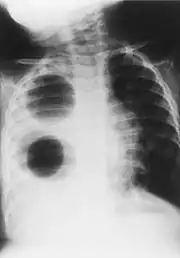

| Chest radiograph of a woman with unilateral pulmonary agenesis | |

- Chest X-ray is effective in detecting the traits of lung herniation.[1] The unaffected side of lung tends to undergo hypertrophy, and move towards the empty space in the chest wall on the opposite side.[1] This herniation could be indicated by fluoroscopy.[1] With age increasing, the herniation progresses and ease its detection.[1]

- Electrocardiogram is useful in detecting dextrocardia, a possible outcome when agenesis is present on the right lung.[1] With empty space in the chest wall, the heart rotates in clockwise direction, shifting the location for apex beat occurrence.[1] Hence cardiac physical examination also helps as heart sounds is heard best at right chest with dextrocardia.[1][4] In the condition of left side agenesis, heart sounds will appear to be louder than normal.[1][4]

- Chest asymmetry, as a possible trait for pulmonary agenesis, is found to be more obvious in adult patients, especially in males.[4] Breast development in females tends to make it less obvious for the observance of asymmetry, though it could still be indicated by a more conical shape and slightly higher location of the breast on the affected side.[4]